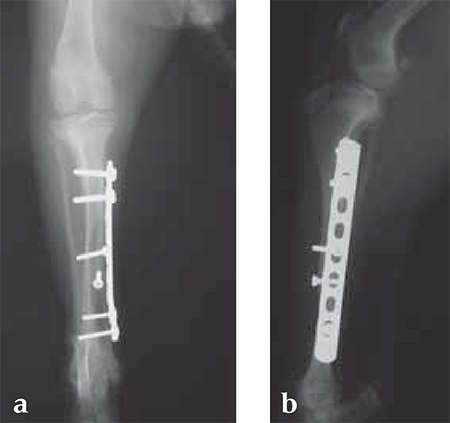

A 12-week-old Yorkshire Terrier, 1.3 kg

(Case provided by Alessandro Piras, Banbridge, Northern Ireland)

Small Bones, Small Plates: Clinical Application of Mini LCP